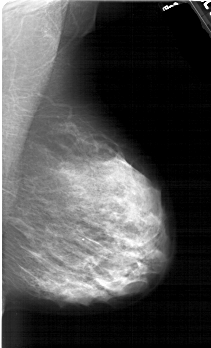

A_1983_1.RIGHT_MLO

RIGHT_MLO LINES 6256 PIXELS_PER_LINE 3796 BITS_PER_PIXEL 12 RESOLUTION 43.5 NON_OVERLAY